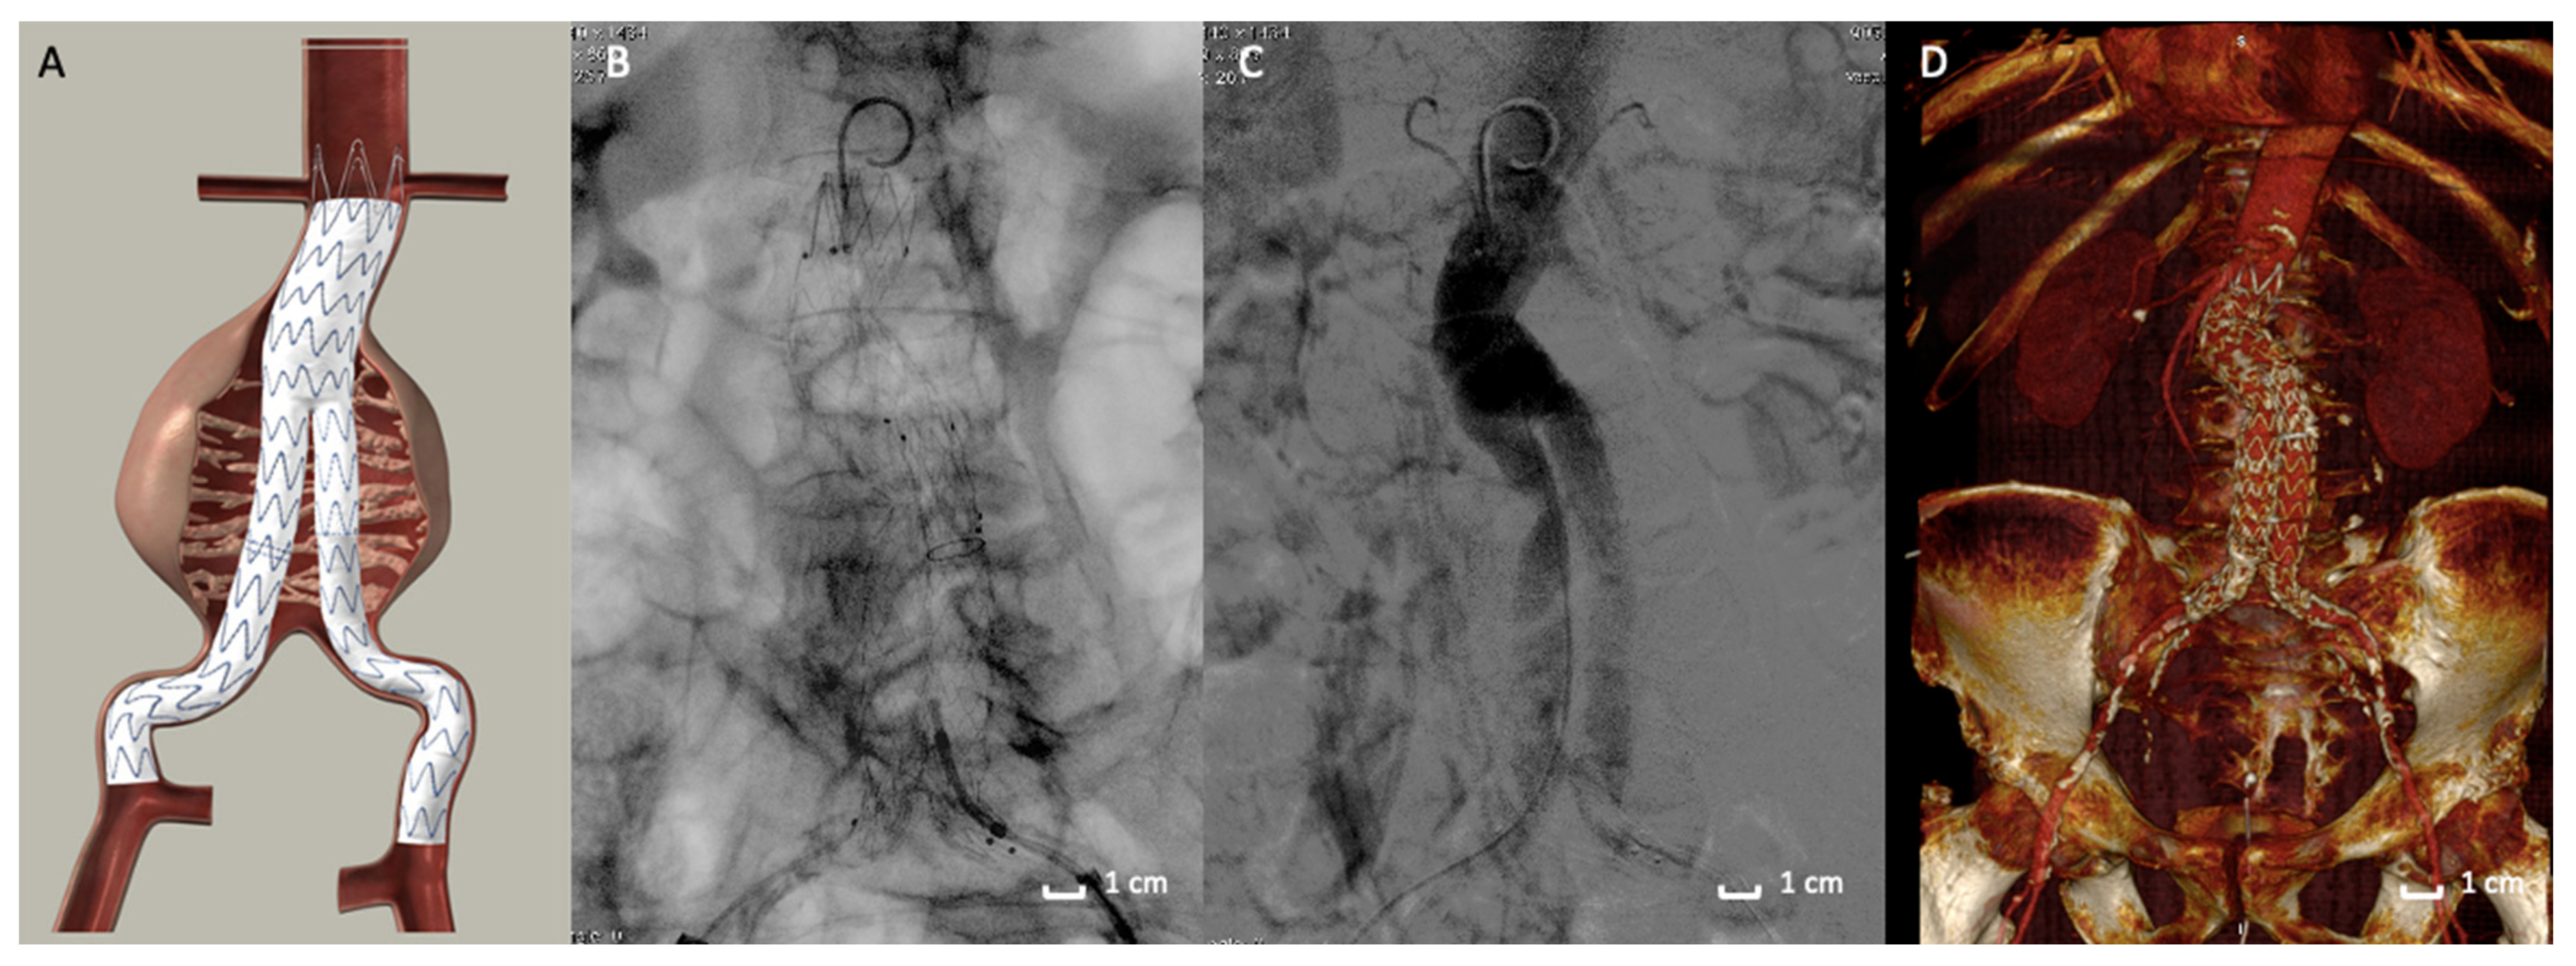

EVAR has gained wide acceptance as the preferred method to treat patients with AAA [1,23,24,25,26,27,28]. The standard endovascular procedure involves a stent-graft that is designed to exclude the aneurysm from the systemic circulation (Figure 1). The stent is made of a metallic skeleton and covered with polytetrafluoroethylene (PTFE) or polyester fabric that keeps the stent impermeable. The device is advanced through the femoral artery using fluoroscopic guidance toward the aneurysm site and then deployed. Sealing the proximal and distal ends of the aneurysm isolates the aneurysm, preventing subsequent rupture. Traditional EVAR devices employ self-expanding stent structures to promote graft-to-aortic wall apposition (seal) and fixation [29,30,31]. The amount of proximal device oversizing with self-expanding stent grafts (SESGs) is known to influences neck progression over time [32]. As a matter of fact, once deployed, SESGs continue to expand until the nominal diameter is reached unless tissue resistance limits expansion. When aortic neck dilation occurs, midterm outcomes are reportedly adverse [33,34].

Figure 1.

Traditional stent-graft design. (A) Picture of the endograft deployed in Abdominal Aortic Aneurysm. Traditional Endovascular aneurysm repair (EVAR) devices employ self-expanding stent structures to promote graft-to-aortic wall apposition (seal) and fixation. (B) Intraoperative fluoroscopic image of the endograft deployed in the abdominal aortic aneurysm (AAA). (C) Angiographic acquisition that reveals a good exclusion of the AAA and the good patency of the endograft. (D) 3D volume rendering of Computed Tomography Angiography at 1-month follow-up that shows the correct aneurysm exclusion.